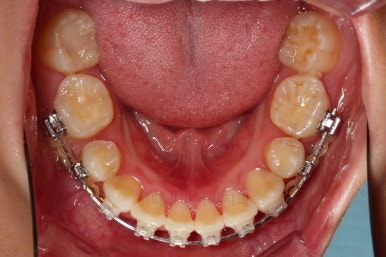

부산무턱교정치과 초진 시 입안의 모습입니다.

전반적으로 치열이 삐뚤고요. 아랫니가 윗니보다 뒤쪽으로 많이 가려져 있죠.

그래서 앞에서 봤을 때 아래 앞니가 거의 보이지 않는 상태인데요.

이런 교합을 "과개교합"이라고 표현합니다.

전반적인 교합, 치열, 과개교합, 튀어나와 보이는 앞니 등을 개선해줘야겠네요.